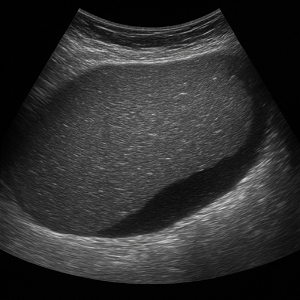

간

간은 복부초음파에서 가장 먼저 살펴보는 장기예요. 초음파로 지방간, 간경변, 결절, 낭종, 혈관종, 간암 등 여러 가지 변화를 감지할 수 있고, 간 기능 검사에 이상이 있을 때 특히 중요하게 확인해요.

간 질환

- 지방간

간에 기름이 쌓이면 초음파에서 밝고 반짝이는 모습으로 보일 수 있어요. 요즘 지방간이 흔한데, 초음파로 쉽게 확인되서 유용합니다. - 간경변

만성 염증으로 간이 딱딱해지고 울퉁불퉁해지는 상태예요. 초음파에서 간 표면이 거칠고 모양이 변형된 모습으로 나타나요. - 간암(간 종양)

덩어리나 혹처럼 생긴 이상이 초음파 화면에 포착될 수 있어요. 양성 종양인지 악성인지 구분하려면 추가 검사가 필요할 때도 있어요.